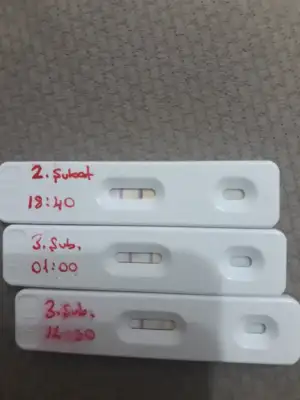

Allah razı olsun çok teşekkür ederim verdiğin bilgiler için. Normalde beslenmeniz nasıldır Eşinnin ve senin?Keçiboynuzu özü 1 hafta boyunca sabah akşam içti . Bide deneme olacağı akşam pekmezini yemişti. Başka yok cnm. Bide testle takip yapmıştım. Ama test yapmadan çatlayacağını hissetmiştim. 6 ay test yapınca alışıyor anlıyor insan